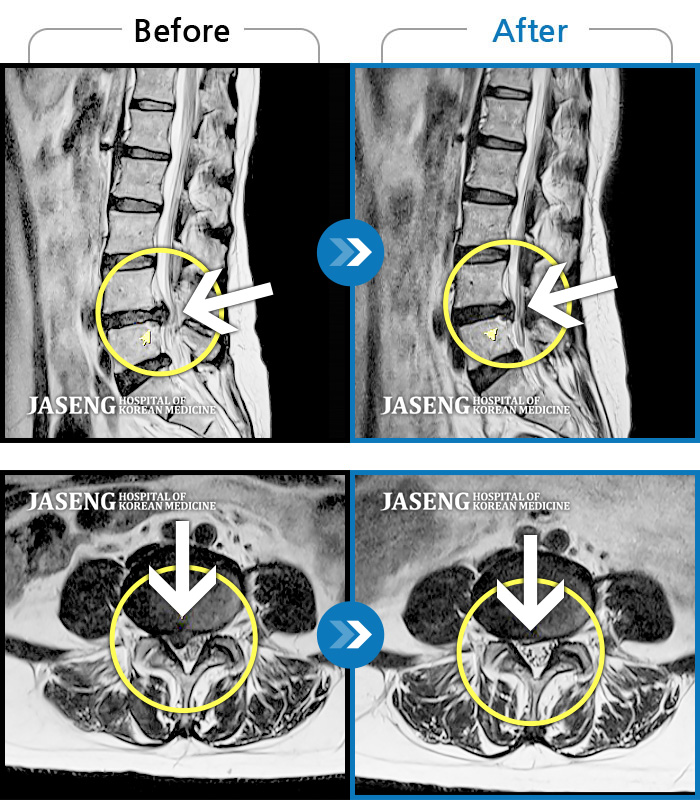

허리디스크

광주 · 김동은 원장

요추 5번과 천추 1번 사이에서 탈출된 디스크가 신경막을 압박

촬영시기

2017.08.26 ~ 2018.03.31

2020.01.23